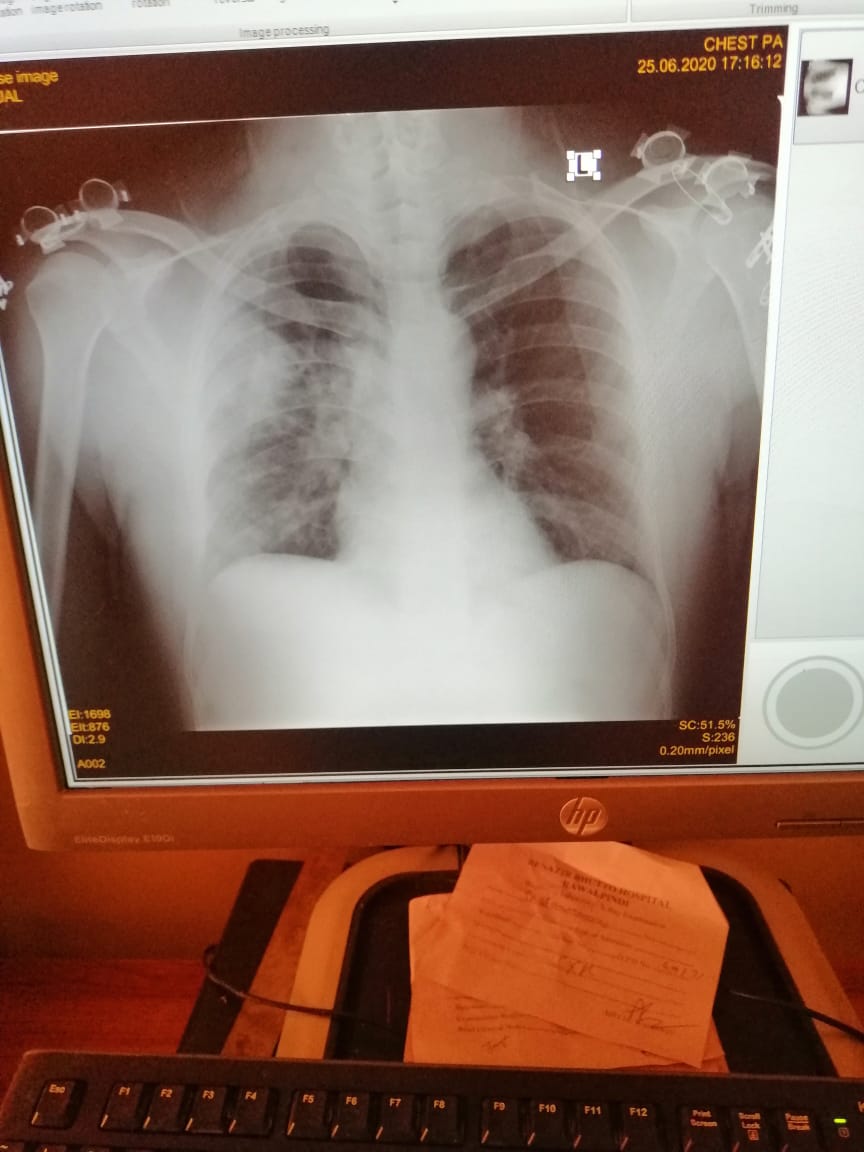

x-ray chest is very bad. please do his CRP CBC procalcitonin ferritin levels LFTs and start him good antibiotics tab me moxiget 400mg OD tablet Panadol injection indrop D once every alternate day for a week than once a week for 8 weeks in warm milk. tab qalsan D x OD tab surbex Z daily keep him in prone position. take him to the hospital as soon as possible for further management

Attach Photo here: